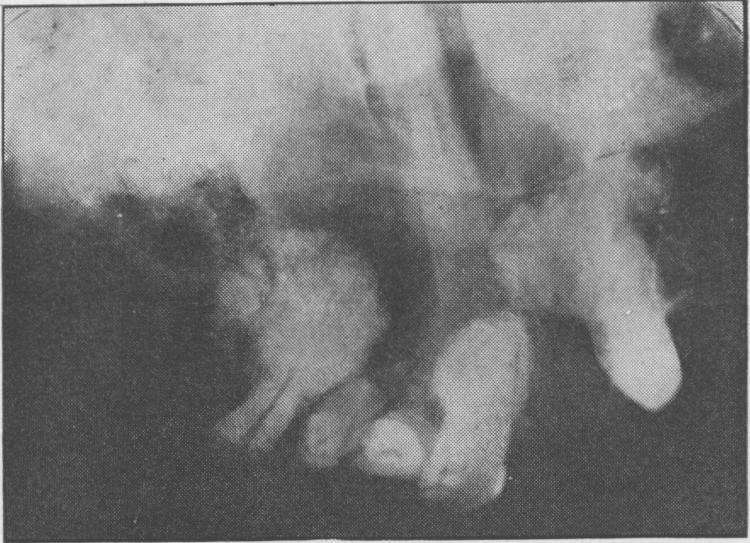

Fibrous dysplasia of bone and comparable conditions in the jaws.

Proc R Soc Med. 1951 Jul;44(7):549-56. doi: 10.1177/003591575104400705.